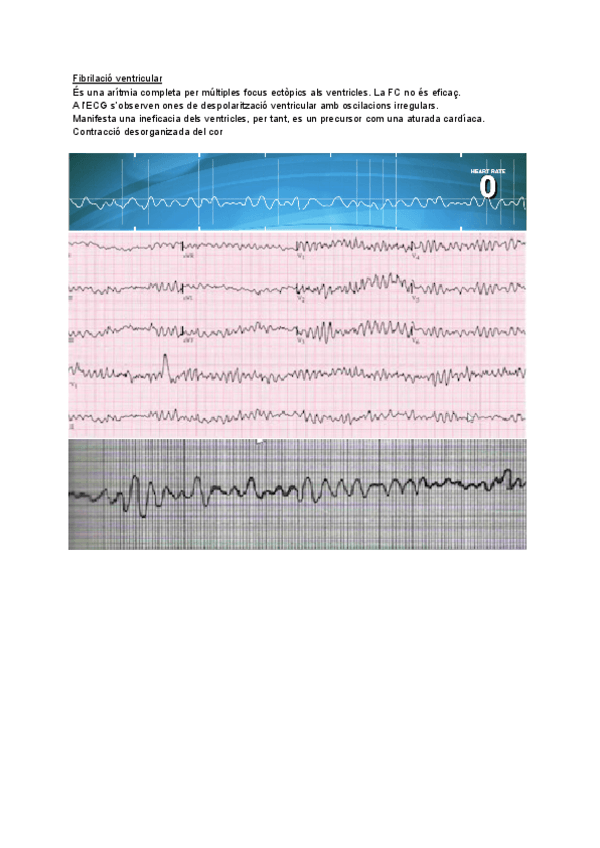

He publicado nuevos apuntes de 4º Enfermedades del Aparato Cardiocirculatorio: ECG.pdf

2 páginas